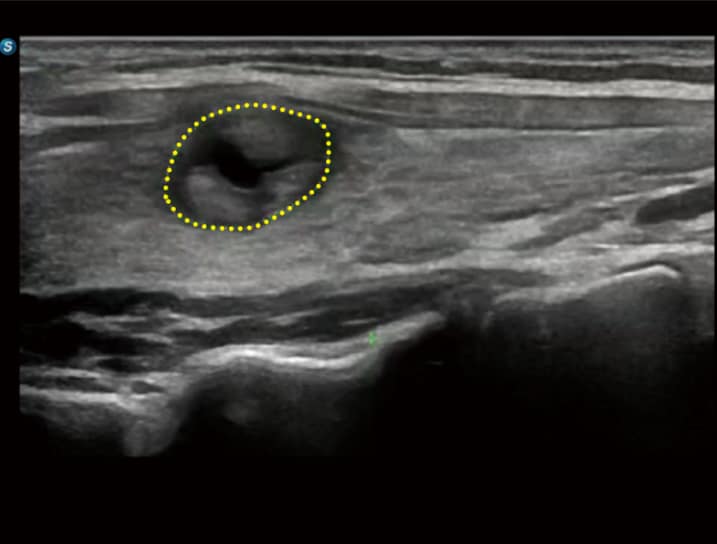

• S-SWE (Shear Wave Elastography): Ermöglicht die quantitative Beurteilung der Leberfibrose inklusive einer Qualitätskarte zur Stärkung des Diagnosevertrauens.

• CEUS HFR: Kontrastmittelverstärkter Ultraschall mit hoher Bildrate zur detaillierten Darstellung von Läsionsperfusionen.

• SonoFusion: Eine wegweisende Technologie, die Ultraschalldaten direkt mit CT- oder MRT-Daten fusioniert, ohne dass externe Sensoren benötigt werden.

• S-Thyroid & T-MSK: Automatisierte Erkennung und Klassifizierung von Schilddrüsenläsionen nach ACR-TI-RADS sowie die Identifikation standardisierter Gelenkebenen im Bewegungsapparat.